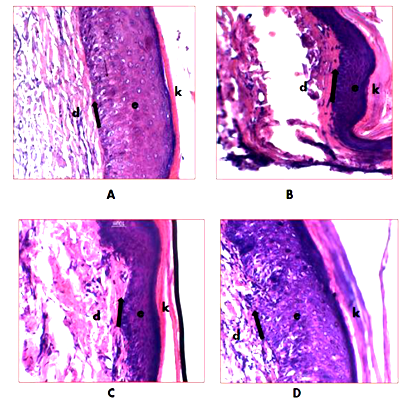

Effect of methanolic extract of Tectona grandis leaves (TGME) on the epidermal thickness of the plantar surface of the hind paw skin in diabetic rats

In normal control rat (A) showing the normal boundary between the epidermis (e) and dermis (d) is marked by a line, layer of keratinocytes (k) an outer surface; diabetic control rat (B) remarkably decrease the thickness of epidermis in diabetic control as compared to the normal control animal. Diabetic rat treated with low dose (250mg.kg‒1) of TGME (C) slightly increased the boundary between the epidermis (e) and dermis (d) is marked by a line, layer of keratinocytes (k) an outer surface; and diabetic rat treated with high dose (500mg.kg‒1) of TGME (D) appear normal thickness of epidermis have equal to normal saline treated rat Figure 7.

Figure 7 Effect of TGME on epidermal thickness of planter surface of the hind paw skin in diabetic rats.